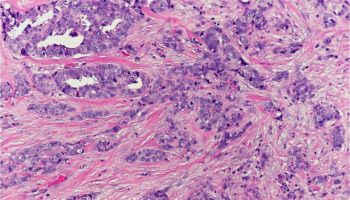

Cancer cells with the ability to invade surrounding tissue and with the potential to metastasize (spread) to lymph nodes and distant organs.

A pattern of growth where the cancer cells grow into (invade) the surrounding tissues (see also infiltrating).

A pattern of growth where the cancer cells grow into (invade) the surrounding tissues (see also invasive).

A histologic description of how closely the cancer cells resemble their normal cell of origin. In the breast, the overall grade score is calculated by looking at the mitotic rate, the nuclear grade or atypia, and the degree of gland formation. The final grade will be either grade 1, 2 or 3. In general, a higher tumor grade is associated with more aggressive behavior.